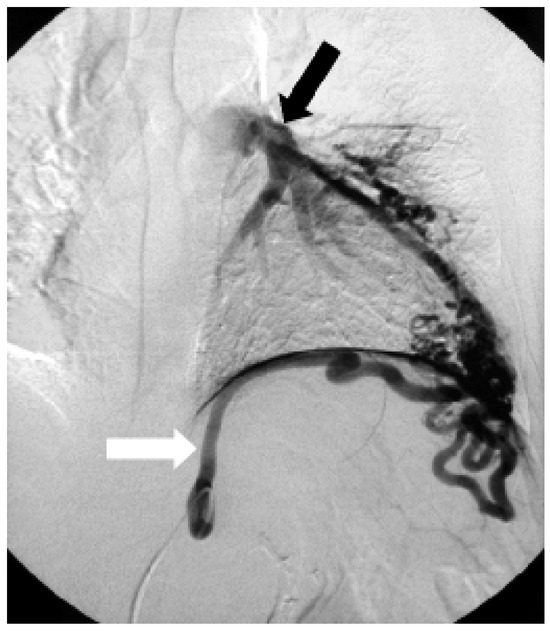

Coronary and Peripheral Thromboembolism from a Giant Left Atrium

by Marcello Di Valentino, Andrea Menafoglio, Ludwig von Segesser, Jeanne-Marie Segatto and Augusto Gallino

Cardiovasc. Med. 2006, 9(1), 28; https://doi.org/10.4414/cvm.2006.01144 - 27 Jan 2006

Abstract

We report the case of a patient with a history of mitral valve replacement and a giant left atrium with acute transmural anterior myocardial infarction and concomitant acute occlusion of the right superficial femoral artery [...] Full article